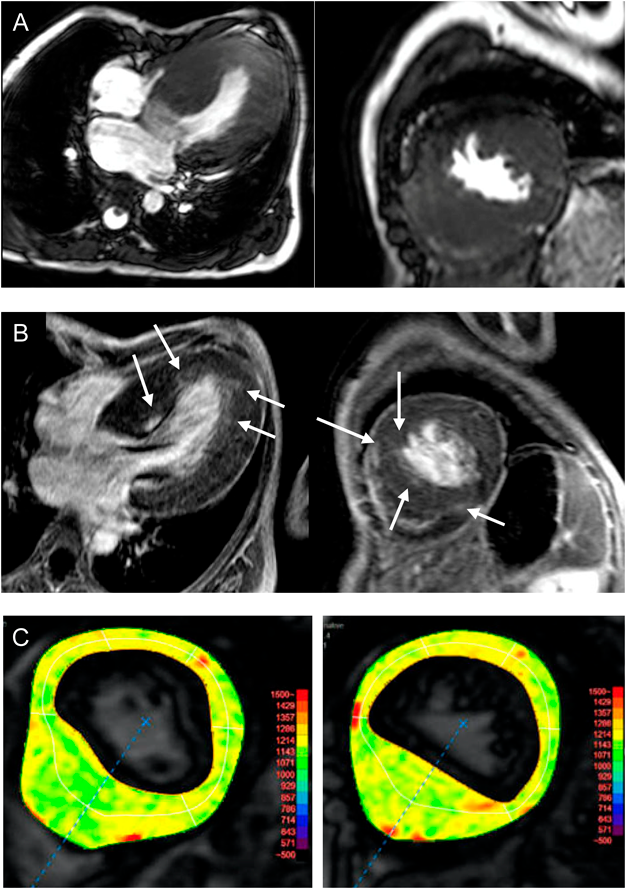

The blood trough concentration of sirolimus in the 16th week after administration was 6.0 ng/mL (effective range, 5–15 ng/mL); therefore, the dose was considered appropriate. Stomatitis occurred during sirolimus administration but did not require special treatment. There were no other side effects that could be attributed to sirolimus administration. Eight weeks after the completion of sirolimus treatment, cMRI was performed (Fig. 3A–C). Significant wall thickening of the entire left ventricle was confirmed using cine MRI. Late gadolinium enhancement (LGE) examination revealed patchy gadolinium enhanced spots in the basal and apical area. T1 mapping revealed elevated native T1 value in the entire left ventricle, suggesting that fibrosis occurred in the entire left ventricle. Echocardiography performed at the same time as the cardiac MRI examination 8 weeks after the end of the treatment showed significant thickened IVS and LVPW with 18 mm each, significant high E/e′ (average) with 24.8, and peak PG of LVOT 137.5 mmHg. No obvious changes could be confirmed from the measured values before treatment. The patient subsequently underwent myectomy because of the limited availability of other medical treatment. The patient’s subsequent course was stable.

Journal of Pediatric Cardiology and Cardiac Surgery 5(1): 30-35 (2021)

Fig. 3 Myocardial properties evaluated by cardiac MRI

A: Cine MRI revealed significantly thickened entire left ventricular wall. B: Spotty positive areas were found in the left ventricle wall (white arrows) through LGE examination. C: An increase in the native T1 value was observed in the entire left ventricle through T1 mapping. Findings reflected entire left ventricle fibrosis. LGE, late gadolinium enhancement; MRI, magnetic resonance imaging.

We administered sirolimus for 16 weeks to a patient with NSML with severe LVOTO, however, no obvious effect could be confirmed. T1 mapping on cardiac MRI confirmed an elevation in T1 value throughout the left ventricle, suggesting that myocardial fibrosis occurred in the entire left ventricle. Myocardial fibrosis is a histological change that occurs in the end stages of heart failure regardless of the cardiac disease. The effect of rapamycin is expected to be exerted by suppressing cell proliferation caused by RASopathy. The effect on the myocardium where fibrosis occurs extensively as in this patient cannot be expected. Therefore, the results may have been different if rapamycin was started before myocardial fibrosis occurred.

Hahn et al. have reported their experience in using a rapamycin analog for treating HCM in NSML infants with a heterozygous Q510 mutation in the PTPN11 gene.10) Although the patient was to undergo a heart transplant eventually, rapamycin treatment had improved the New York Heart Association classification stage and decreased the BNP levels. Based on these findings, it was concluded that rapamycin may be effective for HCM associated with NSML.10) In our case, we could not confirm the changes of measurement values and parameter of cardiac function which was measured by tissue Doppler methods on echocardiography associated with the sirolimus treatment. However, a few points merit discussion: Post-treatment cardiac MRI results suggested that T1 mapping showed elevated T1 levels throughout the left ventricle, suggesting fibrosis occurred throughout the entire left ventricle. However, in LGE, only spot-like contrast findings were observed, and there was a gap between the two methods. While traditional LGE techniques could detect regional variations in myocardial contrast enhancement compared to the normal myocardium, accurate determination of variations becomes difficult when the myocardium is affected widely.11) In addition, it has been reported that about half of HCM patients do not have LGE positive findings.12)

Native T1 mapping is an MRI technique that measures the absolute T1 value of the myocardium. T1 mapping can accurately evaluate myocardial properties even in cardiomyopathy that involves the entire left ventricle.13) Fibrosis of the left ventricular myocardium is caused by a long-term pressure overload. Moreover, myocardial fibrosis was not normalized by the current treatment. Considering the MRI findings, we probably initiated the treatment after the onset of advanced fibrosis rendering the treatment less effective, and the results may have been different if the treatment was initiated at an earlier stage. Furthermore, the RAS/MAPK and AKT/mTOR signaling systems are both complex pathways; even if the signaling system downstream of mTOR is suppressed by an mTOR inhibitor, signals may be mediated through other pathways. Therefore, proliferation or cell hypertrophy may not be completely suppressed with sirolimus treatment alone, and it might be necessary to simultaneously suppress proteins involved in cell growth and differentiation in the AKT/mTOR and RAS/MAPK systems. Addition of agents such as GSK-3β and ERK1/2 to the treatment regimen may be warranted for better treatment of the condition. When should we initiate rapamycin administration? Scharmm et al. have published an interesting study that provides insight on this.14) In their studies of HCM mice models using loss-of-function mutation Q510-SHP2, mice have shown increased cardiomyocyte size, heart-to-body weight ratio and interventricular septum dimeter and cardiomyocyte disarray from the prenatal period. They have also reported that interstitial fibrosis occurred in a 3-month-old heart. Interestingly, these changes could be suppressed when rapamycin was administered early after birth. Based on their findings, rapamycin may be a drug that should be given as early as possible, rather than when general treatment is ineffective. Although the effect of rapamycin could not be confirmed in our case at this time, its effect on HCM associated with NSML cannot be completely ruled out. Further studies are warranted, including the careful selection of cases such as initiating therapy at an earlier stage and/or addition of other agents to the treatment regimen.